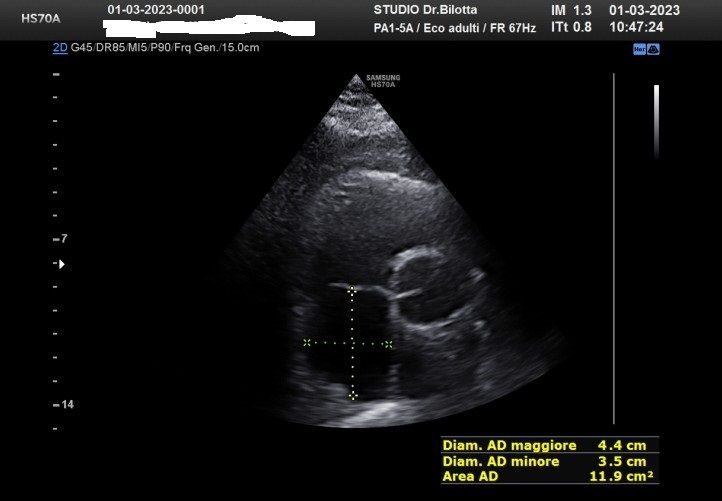

Diploma di maturità classica. Laurea in Medicina e Chirurgia con Lode a 26 anni. Specialista in Oncologia Generale Diagnostica e Preventiva con Lode a 31 anni. Specialista in Malattie Cardiovascolari a 36 anni. Medico generalista dal 1990 poi ospedaliero per trent'anni dal 1993 al 2022 nel corso dei quali ho refertato oltre 100 mila tracciati elettrocardiografici, effettuato oltre 30 mila consulenze specialistiche, praticato circa 10 mila esami ecocardiografici, condotto oltre 2 mila test ergometrici sia su cicloergometro che su treadmill, visionato circa 1500 esami Holter Ecg e ABP ( Ambulatory Blood Pressure ) occupandomi prevalentemente di prevenzione cardiovascolare, ipertensione arteriosa, cardiopatia ischemica, valvulopatie. Dal 2023 ho deciso di trasferire le mie competenze nella libera professione presso il mio studio privato che è stato allestito in linea alle moderne esigenze tecnologiche. Metodiche diagnostiche attualmente praticate: Elettrocardiografia a riposo, Ecocardiografia mono-bidimensionale, PW, CW, Colordoppler tridimensionale, GLS Strain Speckle tracking, Monitoraggio Holter Pressorio delle 24 ore, Monitoraggio Holter ECG 12 canali dinamico delle 24 ore.

Foto e video